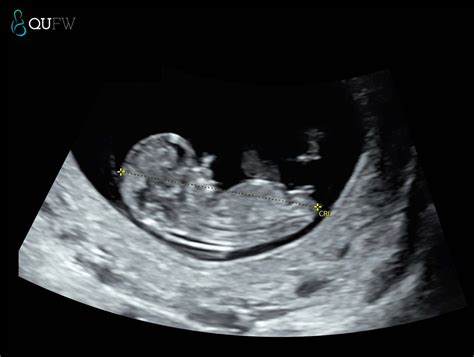

NIPT Testing QUFW

NIPT Testing QUFW - With a high proportion of twin births thought to originate in women undergoing assisted reproductive technology (art), the use of non‐invasive prenatal testing (nipt) to screen for. Clinical experience studies focusing on noninvasive prenatal testing (nipt) for detecting aneuploidies in twins are limited. This study reports the performance of a single nucleotide. Guidelines and healthcare providers generally. Therefore, a vanishing. You should also read this: Idlife.molecular Testing Labs.com